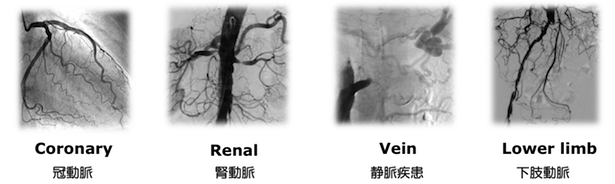

心臓を含め、血液が流れる全身の血管が治療対象です

当院で施行可能なカテーテル治療

- 心筋梗塞、狭心症に対する冠動脈カテーテル治療

- 四肢閉塞性動脈硬化症(間歇性跛行、下肢潰瘍・壊疽)に対するカテーテル治療

- 腎動脈狭窄による腎血管性高血圧、虚血性腎症に対する腎動脈ステント留置術

- 頸動脈狭窄症に対する頸動脈ステント留置術

- 急性動脈閉塞に対するカテーテル血栓吸引療法、カテーテル血栓溶解療法

- 深部静脈血栓症に対する下大静脈フィルター留置術およびフィルター抜去術

- 深部静脈血栓症に対するカテーテル血栓溶解療法およびカテーテル血管形成術

- 中心静脈閉塞、上・下大静脈症候群、腸骨静脈圧迫症候群に対するカテーテル静脈形成術

- 慢性肺血栓塞栓性肺高血圧に対する肺動脈バルーン拡張術

- 大動脈弁狭窄症に対するカテーテル弁形成術(バルーン拡張術)

- 僧房弁狭窄症に対するカテーテル弁形成術(バルーン拡張術)

- 他、血管内異物回収、血管穿孔・小動脈瘤に対するコイル塞栓など